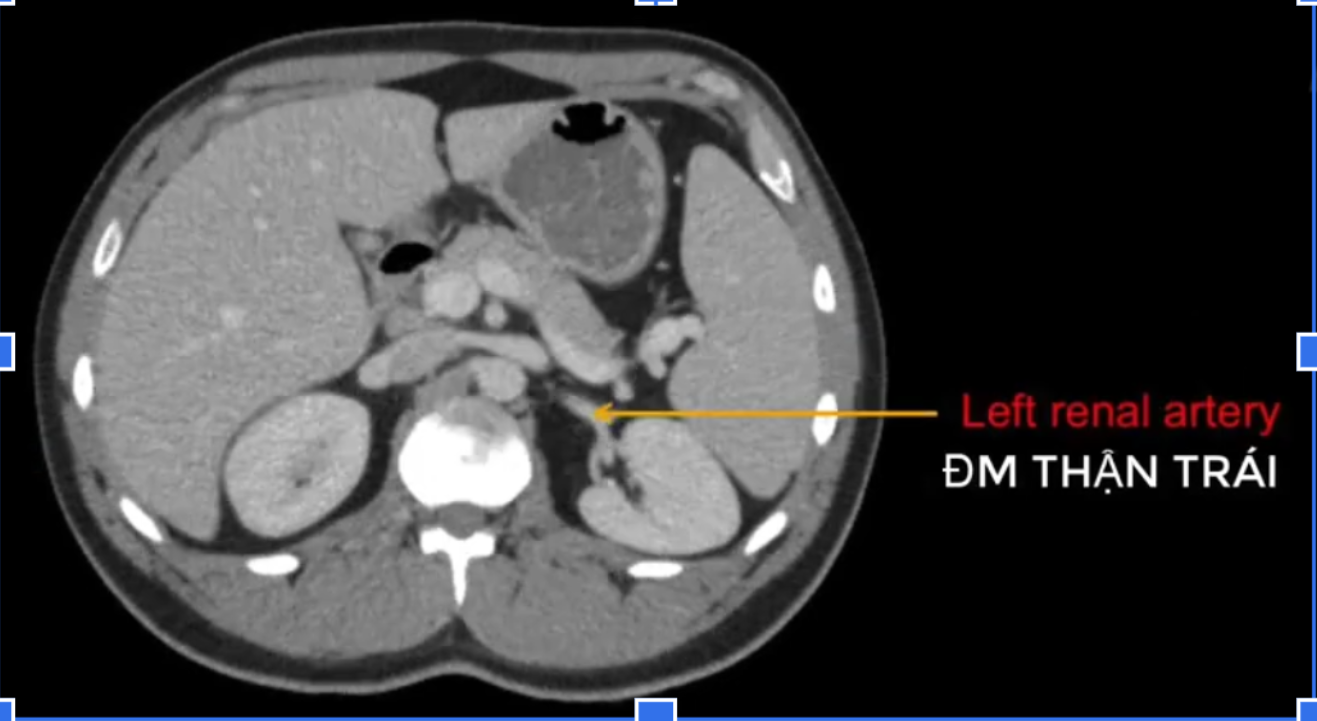

đm thận T?